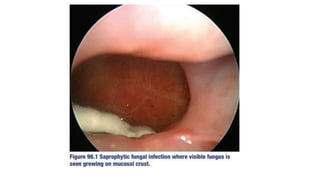

1. Saprophytic fungal infection

• Refers to visible fungal colonisation of

mucus crust seen in nose and PNS on

nasoendoscopy

• Asymptomatic ; foul smelling odour

• May be precursor to fungal ball if

untreated

• Rx- Endoscopic cleaning of infected

crust with or without continued

irrigation with saline water